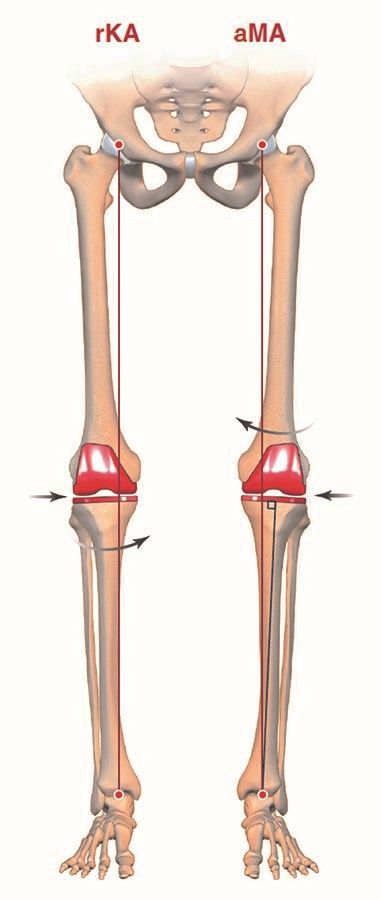

Adjusted mechanical alignment (aMA)

The adjusted Mechanical Alignment (aMA) technique (Figure 6) creates a limb with a residual frontal deformity (varus or valgus). This concept was introduced by Bellemans as “constitutional alignment” (10) and is different to the classical MA and AA concept, which both aim for a neutral mechanical axis. The proposed benefit of aMA is based on the finding that the majority of knees are not neutrally aligned. Correcting them all to neutral will produce a none natural alignment and will need extra soft tissue releases. Adjustments to implant positioning are made on the femoral side only and the tibial implant remains still mechanically aligned in 90° to the mechanical axis. The max residual deformity should not exceed 5°, otherwise the proponents believe that the clinical outcome will get worse and the long-term survival might be reduced. Good clinical outcomes have been reported for aMA-TKA (11,12) but conflicting results have been published by other groups (13,14). So far, no RCT study is available to prove the proposed benefits. Furthermore, the max allowed residual deformity is for debate and the jointline inclination is still not natural.

Restricted kinematic alignment (rKA)

It is highly likely that not all patients are suitable for classical KA. The native anatomy in patients coming for TKA can be biomechanical inferior in terms of severe patho-anatomy in all three dimensions (40–42). This may contribute to primary deterioration and results in complications if the bony pathology is not corrected. Severe constitutional deformity of the limb stretched out ligaments on the convex side (thrust), significant knee joint line obliquity or patellar instability enhanced by an unsuitable knee/limb morphotype are examples for these limitations.

Therefore, some authors have opted for a compromise when performing a TKA on patients with substantial limb deformity. Using computer assisted tools they assess limb frontal alignment and proximal tibial joint surface obliquity during the procedure. They then perform the arthroplasty using the KA technique if constitutional frontal limb deformity ≤ 3° and proximal tibial joint obliquity ≤ 5° obliquity (safe alignment zone) (39). Otherwise, in approximately 40% of cases, the authors adjust the bone cut (tibial and/or femoral) to bring the patient into their safe alignment zone. Otherwise the rKA technique (Figure 9) follows the same principles as the classical KA technique.